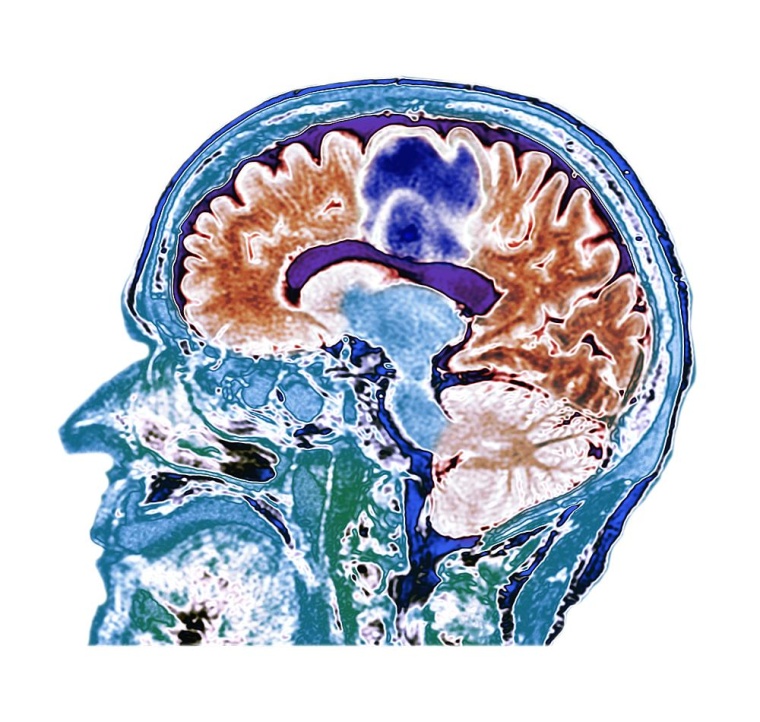

Sollten über 70-jährige Patient*innen mit Kopf-Hals-Karzinomen eine aggressive, kombinierte Strahlen- und Chemotherapie erhalten? Diese Frage ist bei Betroffenen, Angehörigen und auch in Fachkreisen umstritten.

Der Anteil älterer onkologischer Patient*innen nimmt aufgrund der demographischen Entwicklung stark zu. Die Behandlung des Krebsleidens erfolgt gegenüber jüngeren Betroffenen sehr individuell aufgrund von häufigeren und teilweise schweren Begleiterkrankungen, altersbedingt zunehmender Gebrechen und geringeren körperlichen Ressourcen. Hinzu kommen behandlungsbedingte Nebenwirkungen, welche für die Lebensqualität ebenfalls zu berücksichtigen sind. Der Behandlungsstandard bei Kopf-Hals-Tumoren ist entweder die operative Tumorentfernung mit anschließender Strahlentherapie oder eine organerhaltende Strahlentherapie in Kombination mit einer Chemotherapie. Insbesondere der Einsatz einer begleitenden Chemotherapie ist wegen der körperlichen Strapazen und Nebenwirkungen bei älteren Patient*innen sehr umstritten. Studiendaten zur optimalen Behandlung sind bisher kaum vorhanden.